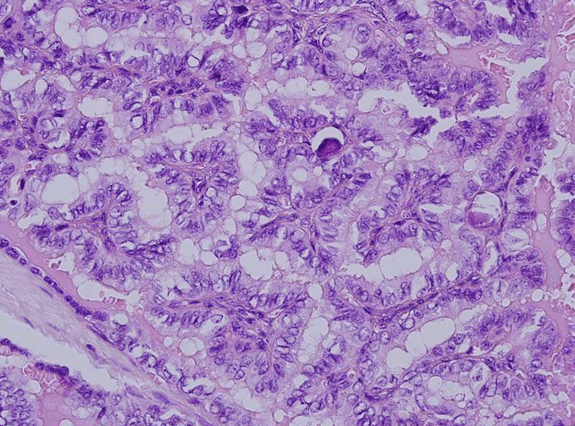

Microscopic examination revealed a cyst lined by respiratory and squamous epithelium. Its lumen revealed a papillary carcinoma, composed of complex, branching randomly oriented papillae with fibrovascular cores and many psammoma bodies. The wall of cyst revealed islands of normal colloid-filled thyroid tissue as well as foci of papillary carcinoma (Figure 2) and (Figure 3). The papillae were lined by cuboidal cells with optically clear and overlapping nuclei, some showing intra-nuclear inclusions and nuclear grooves (Figure 4). The tumor measured 1.1 cm. Connective tissue surrounding the cyst showed many lymphoid aggregates and fibrosis. The tumor was very close to one resection margin. The hyoid bone did not show any tumor.

Figure 4: Papillary carcinoma with characteristic nuclear features and psammoma bodies (H&E stain, x400).